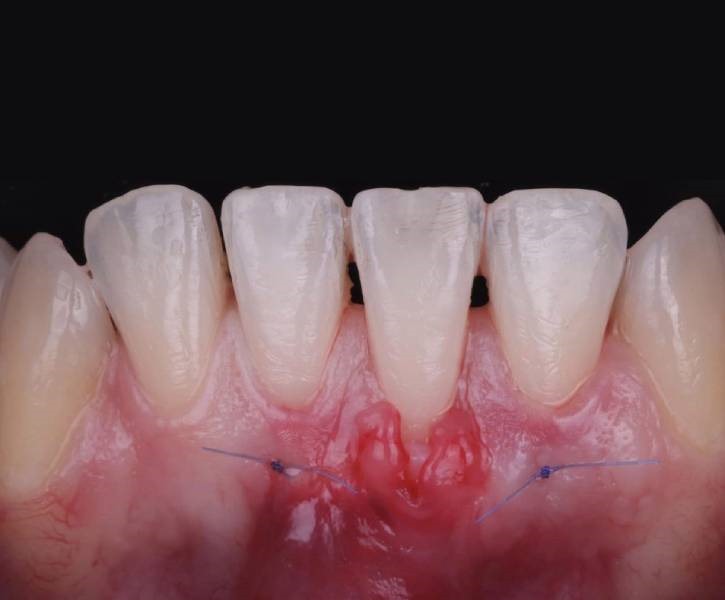

Traditional Gum Surgery

Traditional gum surgery is a time-tested approach used to treat more severe cases of gum disease or structural issues. It involves carefully removing diseased tissue and reshaping the gums for optimal oral health.